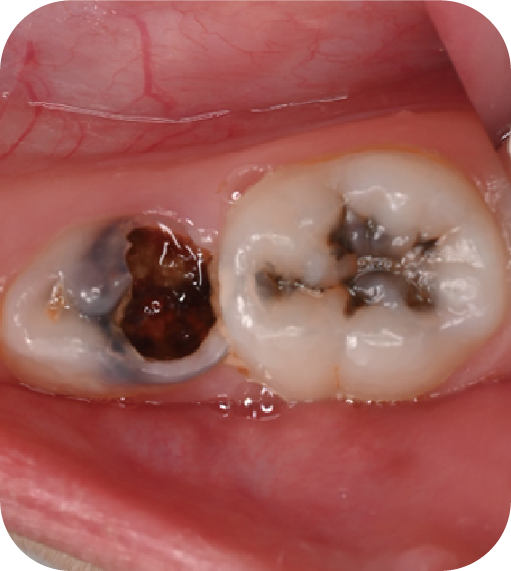

為什么要做窩溝封閉?

后磨牙,也就是大牙咬合面上凹凸不平的裂隙,這就是“窩溝”。窩溝有很多形狀,有的是狹長(zhǎng)的裂隙形狀,還有的在牙齒深處又會(huì)分成幾條小溝。這些地方用牙刷很難深入清潔,于是就成了衛(wèi)生死角,細(xì)菌特別喜歡在里面生存,不斷產(chǎn)酸腐蝕牙齒,蛀牙就這樣產(chǎn)生了。如果我們用窩溝封閉把這些衛(wèi)生死角封起來(lái),那既可以杜絕食物和細(xì)菌進(jìn)入窩溝內(nèi),也可以讓窩溝處的清潔變得更簡(jiǎn)單,這就是做窩溝封閉的目的。同時(shí)它也是世界衛(wèi)生組織、國(guó)家衛(wèi)健委都推薦的防齲方法。